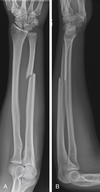

ESSEX-LOPRESTI

1. Fracture of radial head

2. Disruption of interosseous membrane

3. Dislocation of DRUJ

- Results from longitudinal (axial) compression of forearm